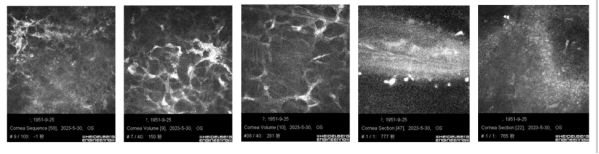

IVCM:右眼角膜上皮局部缺失,炎性细胞及树突状细胞可见,神经未见。基质局部高反光,少量炎性细胞浸润,神经可见,内皮细胞可。

图片